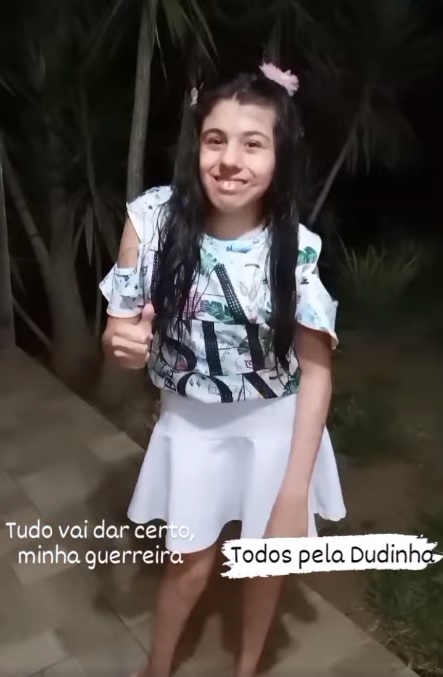

Moradora da localidade do Morro Negro, interior de Taquara, Maria Eduarda Vianna Correia, mais conhecida como Dudinha, tem 13 anos e sofre com as sequelas da Síndrome de Cornélia de Lange. Preocupados com o avanço da doença, que provoca uma série de comprometimentos físicos, cognitivos e neurológicos, Denise Silva Vianna e Fábio Júnior dos Santos Correia estão lutando contra o tempo para arrecadar R$ 200 mil, o valor necessário para a cirurgia que poderá salvar a vida de sua filha.

“Em fevereiro de 2017 minha filha recebeu o diagnóstico de escoliose tridimensional, que deixa a curvatura da coluna em S. Quando diagnosticada estava com 62°, atualmente está com 130° aproximadamente, e vem progredindo cada dia mais”, conta a mãe da Dudinha.

Além da dificuldade motora, essa progressão no grau da coluna faz com que a caixa torácica se modifique, comprimindo os órgãos e agravando ainda mais a situação da criança, que estuda no 5º ano da Escola Municipal de Ensino Fundamental (EMEF) Arlindo Martini e também na Escola de Educação Especial Lucas Sauer, ambas em Taquara.

“Essa cirurgia permitirá que nossa menina volte a correr e brincar, como uma criança normal, tendo uma vida sem dores. O problema é que pelo SUS é muito demorado e a Dudinha não poderá esperar muito tempo. Essa compressão que a caixa torácica está causando em seus órgãos, se não for contida a tempo, poderá causar a morte de nossa filha”, lamenta Denise.